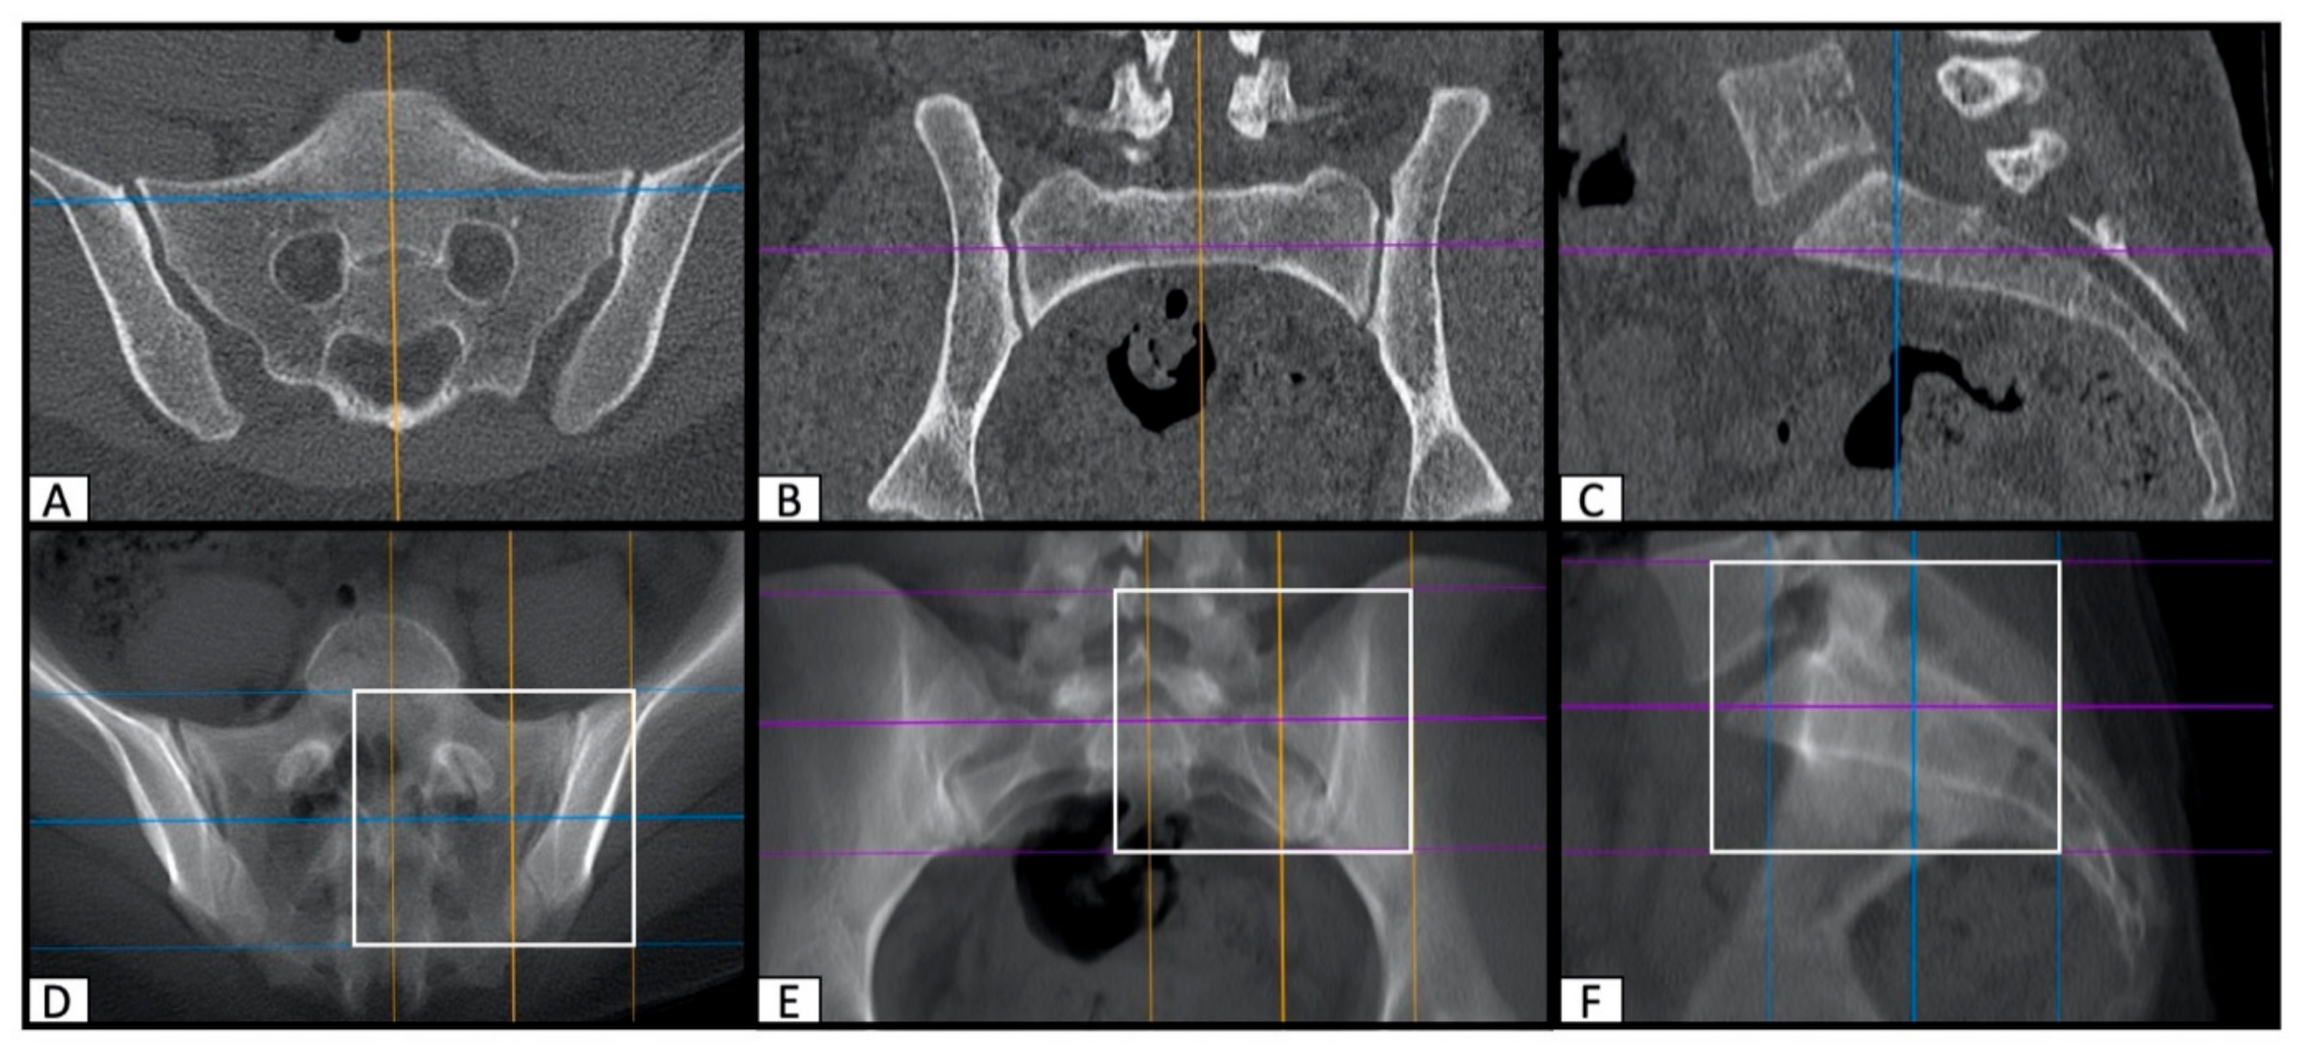

2.2. Image Processing with the Slice Fusion Method

2.3. Determination of SI Screw Corridor Entry- and Endpoint and Direction